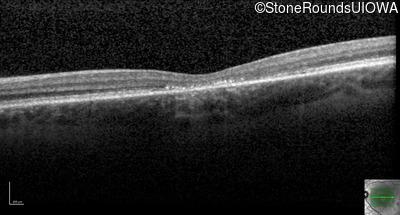

Optical Coherence Tomography - Right - 20/200

Exemplar / OCT Stack